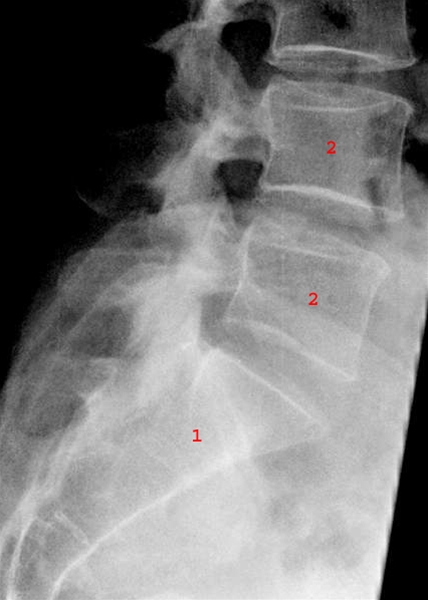

Lænd og korsben, røntgen, sidebillede

Normalt sidebillede af os sacrum (1) og de lumbale ryghvirvler L4 og L5 (2).